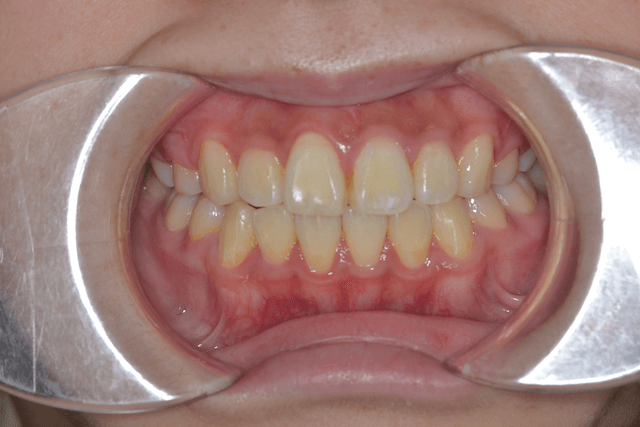

叢生を抜歯とDBSで改善した症例

※DBSとはダイレクトボンディングシステムと呼ばれており、ブラケットにワイヤーを通して歯を動かしていく矯正治療です。

患者情報

17歳女性

主訴

歯並びがガタガタ

行った治療内容

上下顎両側4番抜歯、DBS

治療のリスク

歯肉退縮、歯根吸収

治療期間

動的治療期間3年6か月

※ クリックして拡大することができます。